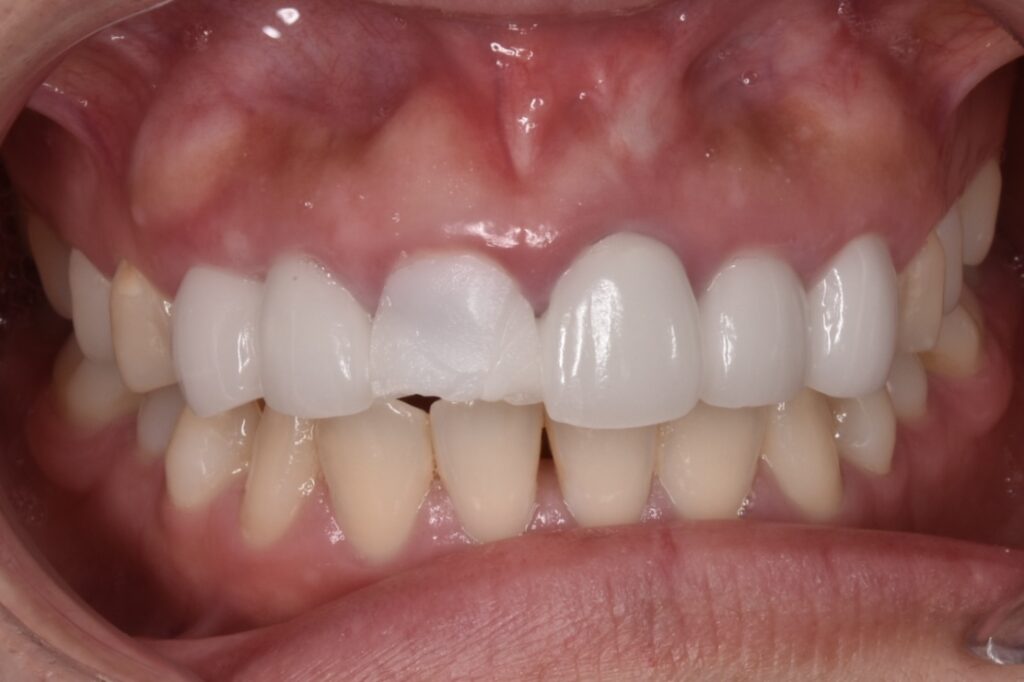

20代女性 20代前半の頃大阪にある有名審美歯科で前歯6本のセラミック矯正治療を受けた。強い痛みはないが、歯茎は赤黒く腫れていて真ん中で割れて、すでに連結してあるセラミックが脱落している状態です。とご相談くださいました。

白い6連結のセラミックがありますが、右側のセラミックの前歯は破折しています。(写真左)また6連結の中央でジルコニアのフレームごと破折していることも確認できます。(写真中央)左の前歯は神経処置がされておらず穴だけ開いた状態でした。(神経治療途中?)土台6本全てが茶色から黒色に変色している事が周囲の天然歯と比べてもわかります。

前歯の歯ぐきの高さがチグハグだったため、歯肉整形をさせて頂きました。歯ぐきの位置を整え綺麗に見えるようにしています。

仮歯は歯の位置が変わらないように連結で製作しています。